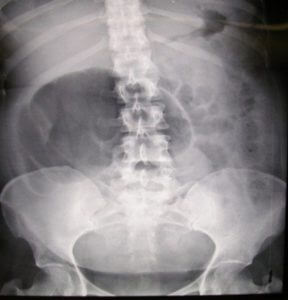

Investigadores estimam que atualmente o número de casos de bebés nascidos por cesariana, devido ao problema de pélvis estreita, aumentaram desde os anos 60 de 3%, de 30 casos em cada mil, para 36 casos. Em termos de evolução, no passado, estes genes que impossibilitariam o parto, não seriam transmitidos de mãe para filhos, já que os dois teriam falecido no momento do parto.

Uma das conclusões é que os bebés tendem a nascer maiores, o que significa nascerem também mais saudáveis. No entanto, o aumento do volume significaria mais problemas no parto natural, o que teria sido desastroso para a mãe e o bebé no passado e os genes não teriam sido transmitidos. ‘Sem a intervenção médica, estes problemas era frequentemente letais, e são, a partir de uma perspectiva evolucionária, uma seleção. As mulheres com o problema de pelvis estreita não teriam sobrevivido há 100 anos. Agora sobrevivem e transmitem o problema codificado nos seus genes às suas filhas.’

É uma questão colocada há muito, o motivo da pélvis não ter aumentado no decurso da evolução humana. O tamanho da cabeça de um bebé humano é grande, quando comparado com outros primatas. Os macacos, por exemplo, têm partos geralmente sem problemas.